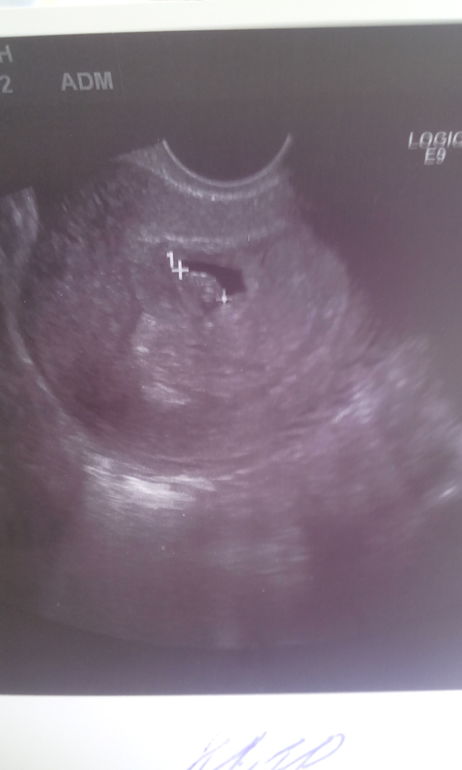

Девочки, пишу сквозь слёзы.. Утром ездила на УЗИ, сегодня ровно 6 акушерских недель, думала порадуюсь, что наконец мне скажут про сердцебиение, размеры малыша и прочее.. Но от услышанных слов Замершая до сих пор не могу придти в себя.. Отчего это происходит не могу понять, всё ведь соблюдаю и делаю правильно, в чём причина?? И стоит ли верить? Меня ничего не беспокоит, выделений нет, грудь болит, ХГЧ недавно сдавала, растёт в хорошей пропорции.. Буду делать через пару дней повторное УЗи, поддержите у кого на моём сроке тоже не увидела сердцебиение, но всё было хорошо потом? Добавила фото.

А вот еще показатели из УЗИ:диаметр желточного мешочка 3 мм — это мешочек, поддерживающий жизнедеятельность плода. То, что он есть, это хорошо!деформация плодного яйца до 12 мм — Я так понимаю, что диаметр плодного яйца 12 мм, для такого срока оно нормальных размеров, но деформированно, что может говорить об угрозе.ктр 9 мм — Вот это больше всего смущает. Так обозначается размер эмбриона от темени до копчика. Эмбрион крупный и что самое печальное, что при таких размерах обычно уже визуализируется мерцание сердечка и прослушивается сердечный ритм. Но надежда на ошибку есть и поэтому нужно обязательно узи переделать. Даже не стоит ждать долго, дня через 2 уже можно переделать.толщина хориона 6 мм — это толщина строящейся будущей плаценты. Здесь не могу судить о норме, но вроде все нормально.Кто разбирается? Ничего не смыслю..У меня в предыдущую Б, которая прервалась на более позднем сроке, в 5 нед и 6 дн еще не было эмбриона, через неделю он появился 4,5 мм с четким сб.В эту Б, в 5,6 нед, эмбрион увидели, 1,3 мм, совсем крошечный, но кордиальная пульсация была зарегистрирована.Просто сходите повторно к хорошему специалисту на хороший аппарат. Держу за Вас кулачки!

А вот еще показатели из УЗИ:диаметр желточного мешочка 3 ммдеформация плодного яйца до 12 ммктр 9 ммтолщина хориона 6 ммКто разбирается? Ничего не смыслю..